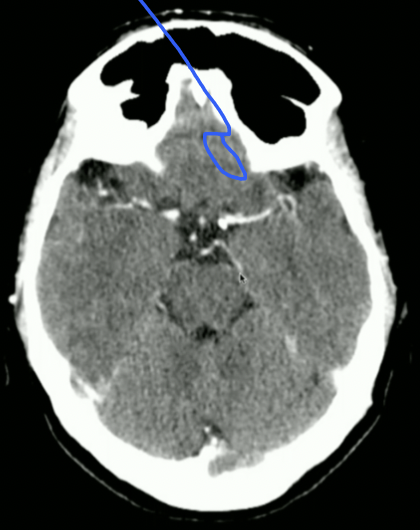

<p>What is this?</p>

What is this?

Basal Nuclei

<p>What is Top + Bottom Circle + Arrow?</p>

What is Top + Bottom Circle + Arrow?

• Top: 3rd Ventricle

• Bottom: 4th Ventricle

• Arrow: Cerebral Aqueduct